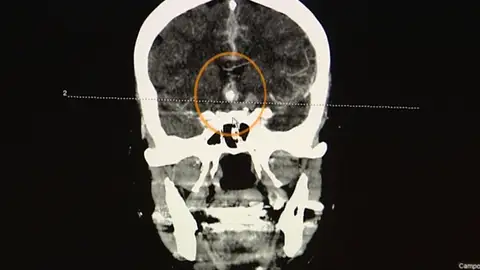

En el Día Mundial del Ictus, 43 hospitales españoles están realizando pruebas de prevención de esta patología que sufren cada año, en España, 130.000 personas. Se trata además de la segunda causa de muerte en nuestro país, la primera en el caso de las mujeres.

El objetivo es sensibilizar a la población sobre la importancia de mejorar la prevención frente a los accidentes cardiovasculares. El ictus constituye la primera causa de muerte entre la población femenina y la segunda entre la masculina.

En España, cada año 130.000 personas sufren un ictus. En torno al 30% fallece, y cerca de un 40% sufre una discapacidad grave.